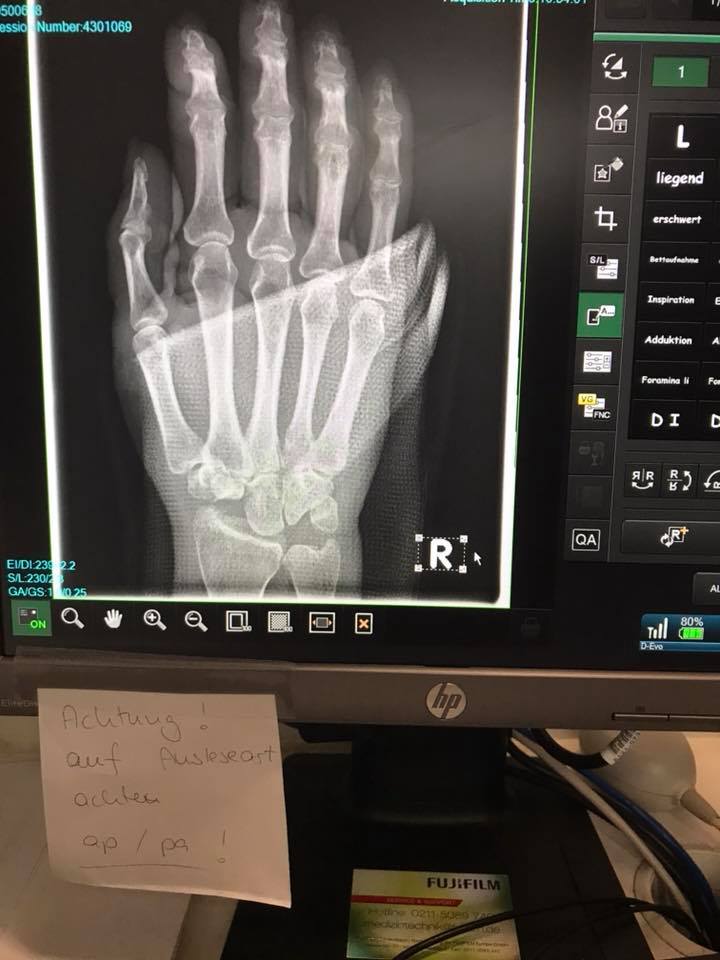

Also meine Geschichte fängt an vor ca 2 Jahren ich hatte öfters Handgelenk Schmerzen und dachte am Anfang selber das ich mich überanstrengt habe, später kamen dann Empfindungsstörungen in den Fingern hinzu, als ich beim Neurologen war zum Karpaltunnel messen hieß es,ist alles okay kommt bestimmt vom Rücken. Ein Jahr später wurde es schlimmer,es wurde wieder gemessen und es war nichts, dann bekam ich einen Nerven Ultraschall auch nichts, danach ein MRT in der Schulter und da wusste ich schon das dort nichts sein kann. Also ab zur Chirurgin und diese sagte das es ein Karpaltunnel wäre den könnte man nur nicht messen, das würde vorkommen, danach wurden die Beschwerden nicht besser sondern eher schlechter. Also wieder zum Doc der sagte das ist normal, es wäre eine Handop und diese braucht ihre Zeit, das ging dann etwa so vom 4.4.2017 bis 2.2.2018. Da sagte dann mein Orthopäde das es jetzt wirklich zu lange ist und verordnete ein MRT der rechten Hand mit Handgelenk und am 13.2.2018 hatte ich meine Diagnose LM. 3 Monate Ruhigstellung danach noch 2 Monate nicht belasten und dann am 2.8.2018 OP in Frankfurt , in der Uniklinik bei Professor Dr.Frank und zwar habe ich mich für eine PRC entschieden ,in der Zwischenzeit wurde ein MRT der linken Hand gemacht und da ist auch schon der Anfang einer LM zu sehen aber wirklich noch sehr früh.